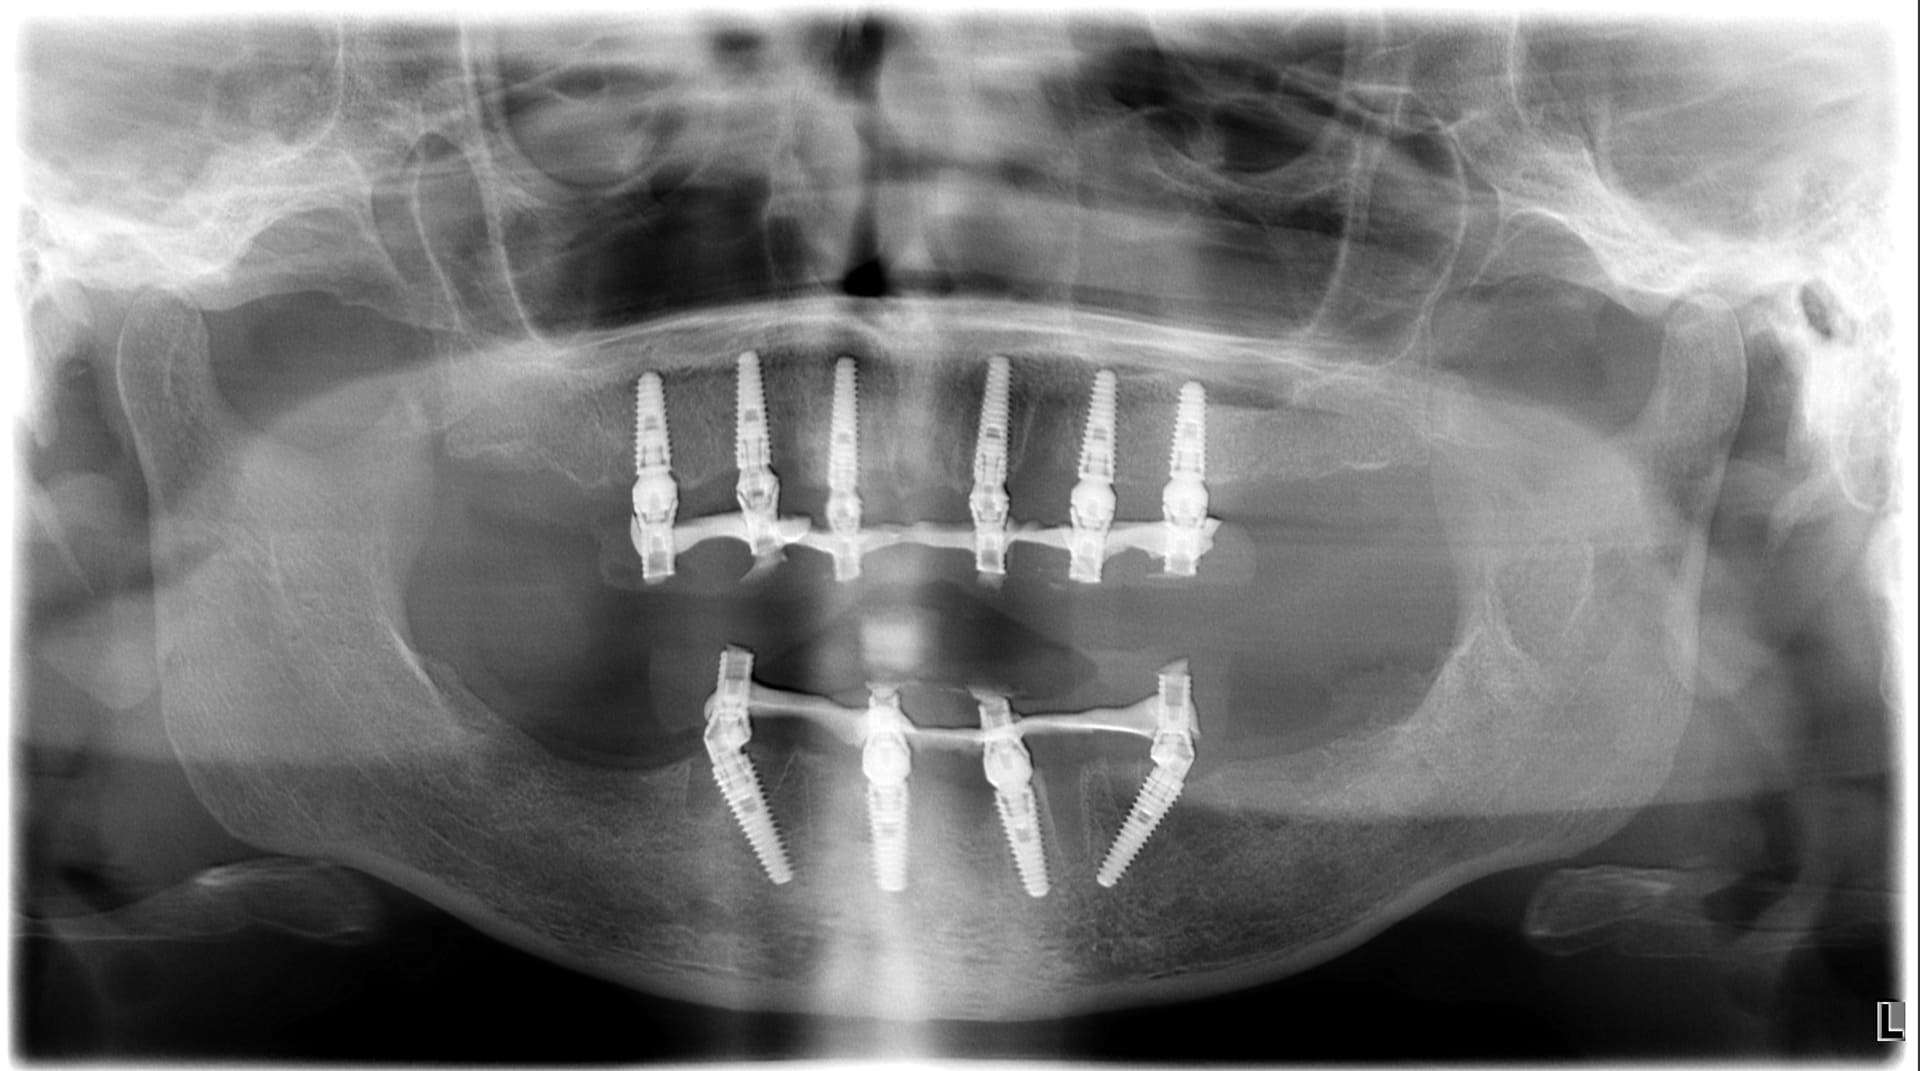

Paziente 1

Dopo >